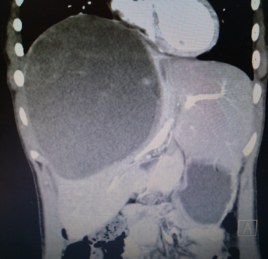

1月8日,自贡市第四人民医院肝胆外科成功完成一例儿童罕见巨大复杂肝恶性肿瘤切除手术,手术顺利,患儿已在康复中。

来自四川宜宾的13岁女孩乐乐(化名),体重60斤,去年7月中旬在当地医院检查发现肝内巨大肿瘤。

由于肿瘤巨大,压迫肝脏主要血管并侵犯膈肌,辗转多家医院都被告知,进行手术切除治疗风险巨大。

市四医院肝胆外科团队进行了详尽的术前讨论,制定了周密严谨的手术计划,拟对患儿施行前入路右半肝切除术,把可能出现的各种影响因素均考虑在内,并备有相应预案,尽最大努力保证患儿安全。

在经过周密手术准备和规划后,由肝胆外科主任赖钊指导,副主任医师陈杰主刀,副主任医师赵斌担任一助,历时四小时完成肝脏肿瘤切除手术。切除的肿瘤重达近4斤,手术中出血却不到200ml。

术后病检提示该肿瘤为肝母细胞瘤,这是自贡市第四人民医院肝胆外科成立以来所切除的第一例肝母细胞瘤。